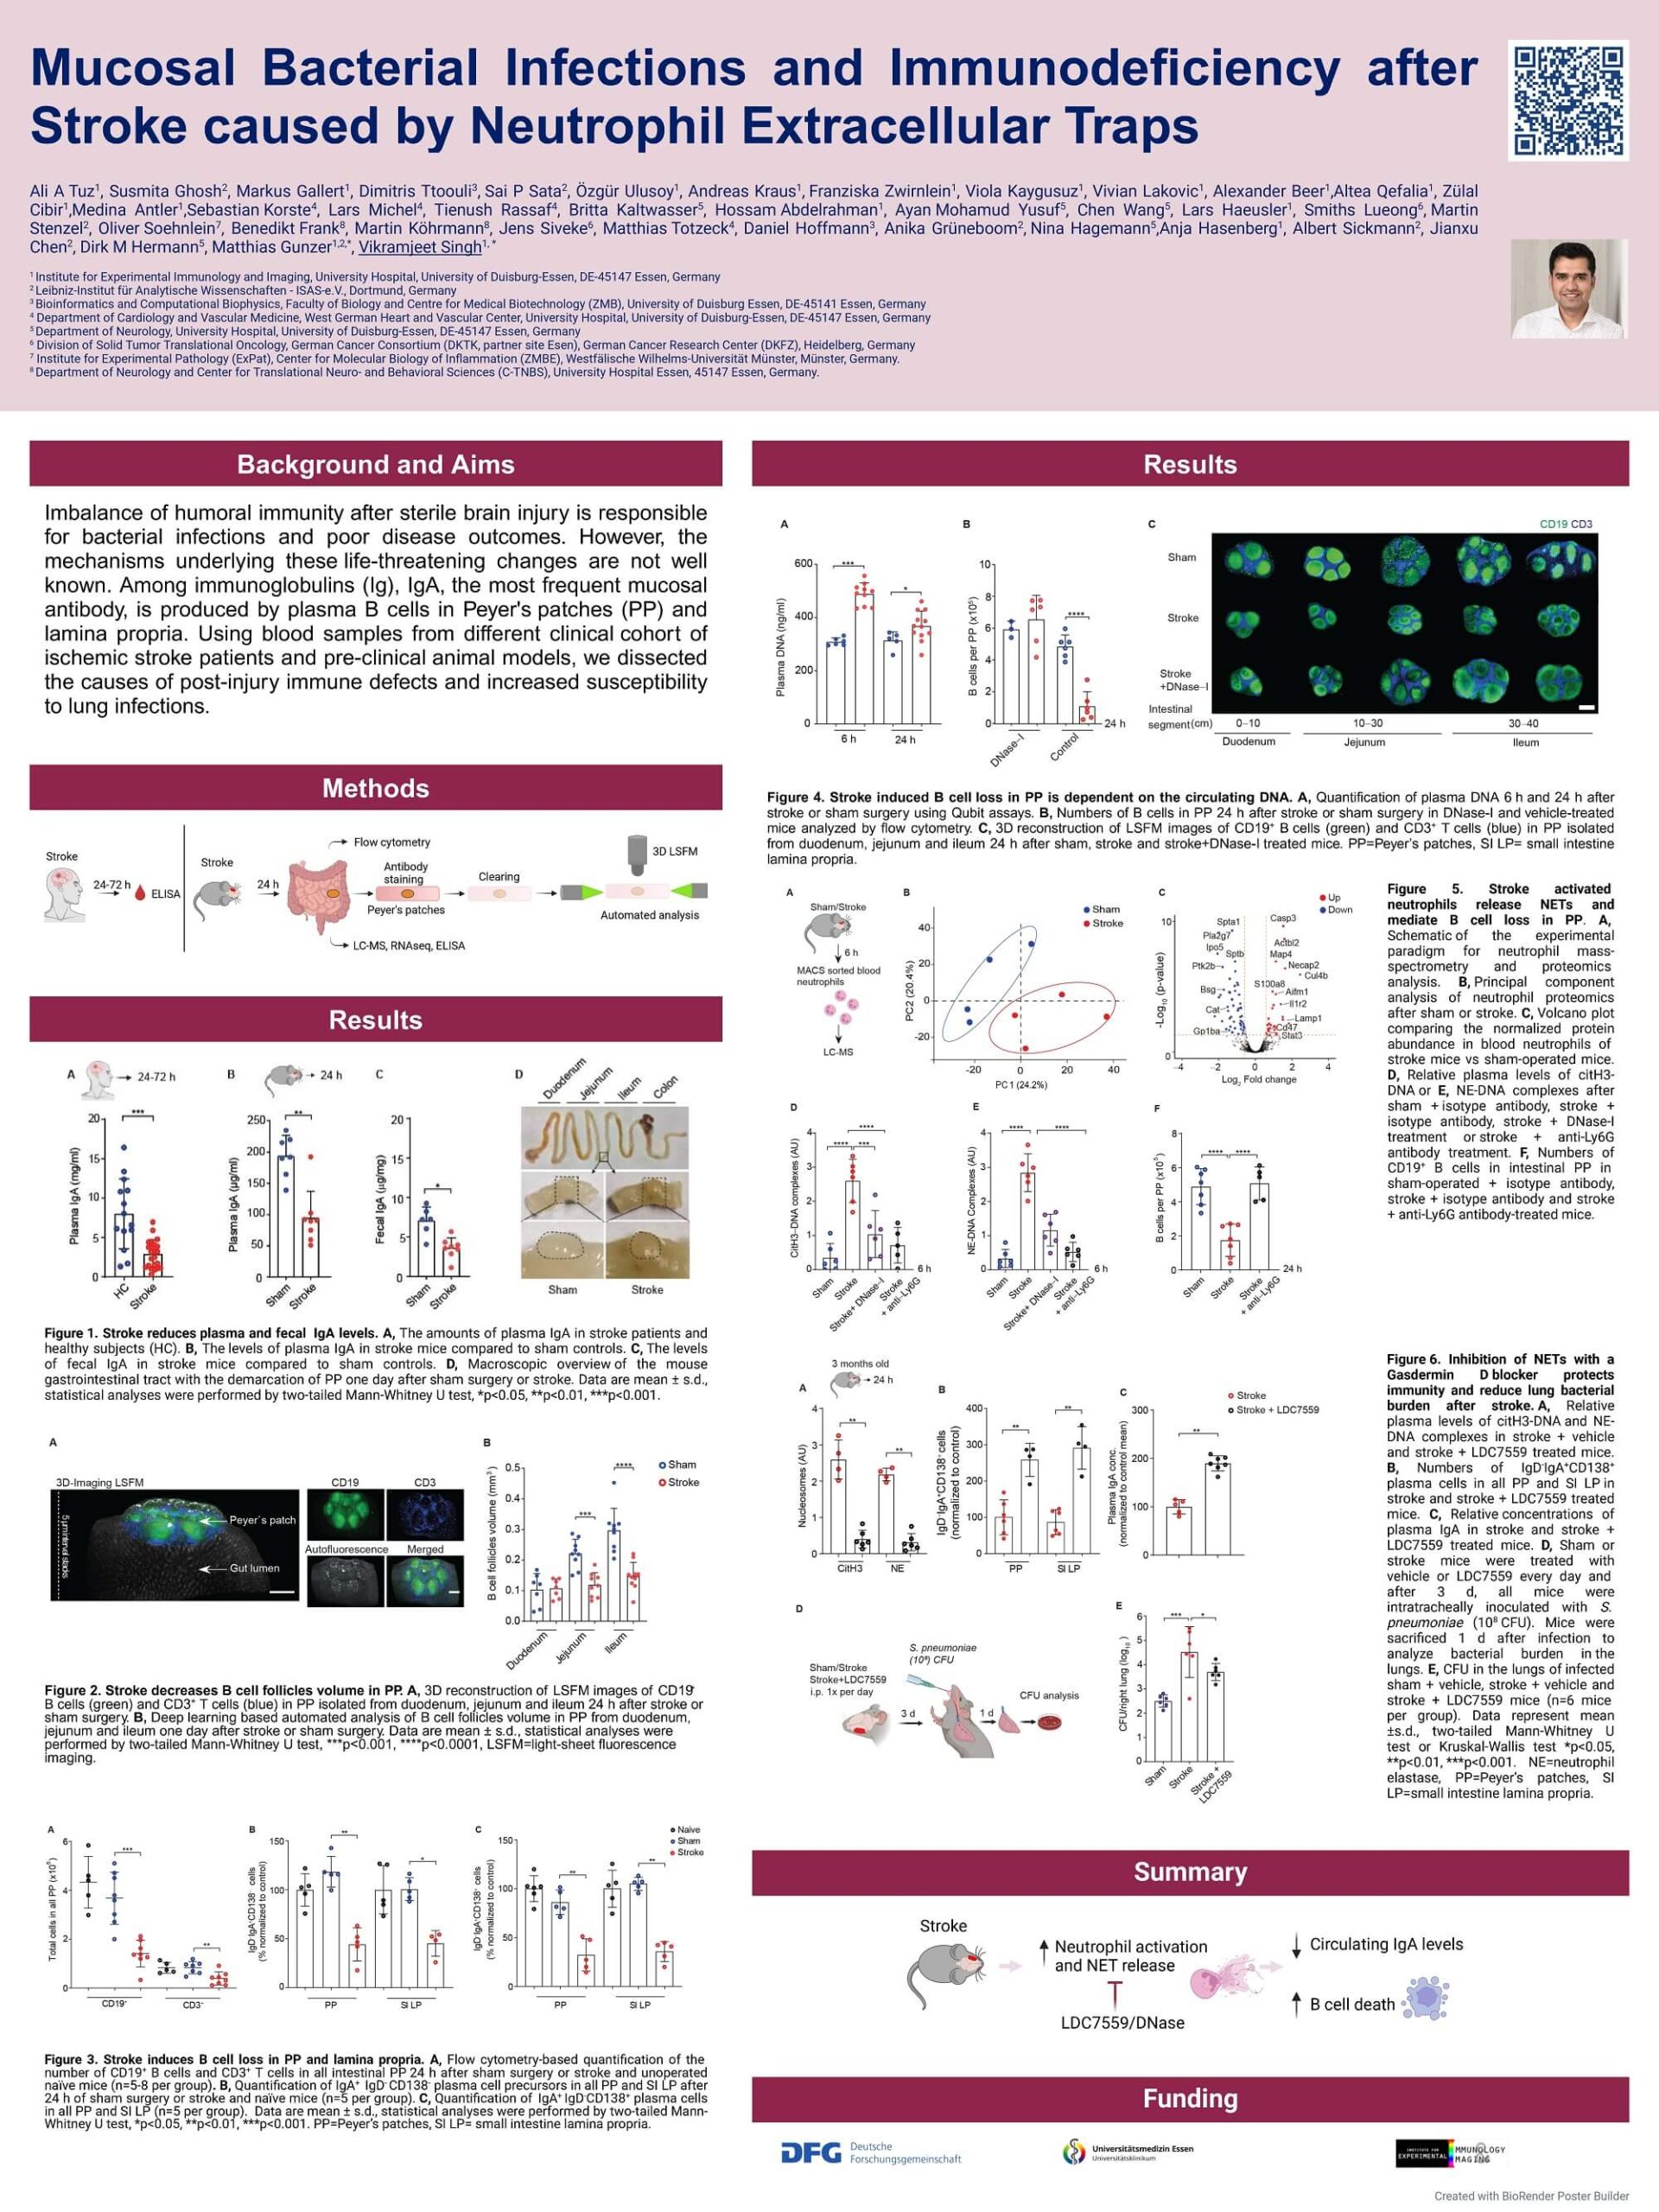

1. Tuz A, Ghosh S, Karsch L, Antler M, Lakovic V, Lohmann S, Lehmann A, Beer A, Nagel D, Jung M, Hörenbaum N, Kaygusuz V, Qefalia A, Alshaar B, Amookazemi N, Bolsega S, Basic M, Siveke J, Heiles S, Grüneboom A, Lueong S, Herz J, Sickmann A, Hagemann N, Hasenberg A, Hermann D, Gunzer M, Singh V. Gut microbiota deficiency reduces neutrophil activation and is protective after ischemic stroke. J Neuroinflammation 2025 May. With DFG funding.